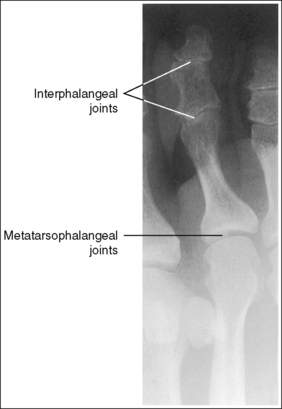

See Figures 6-8 and 6-9 and Box 6-4.

FIGURE 6-8 First lateral toe projection with accurate positioning. DIP, Distal interphalangeal; MTP, metatarsophalangeal.

FIGURE 6-9 Second lateral toe projection with accurate positioning. DIP, Distal interphalangeal; MTP, metatarsophalangeal; PIP, proximal interphalangeal.

The digit is demonstrated in a lateral projection. The posterior surface of the proximal phalanx demonstrates more concavity than the anterior surface, and the condyles are superimposed. The soft tissue outline of the nail, when shown, is in profile anteriorly.